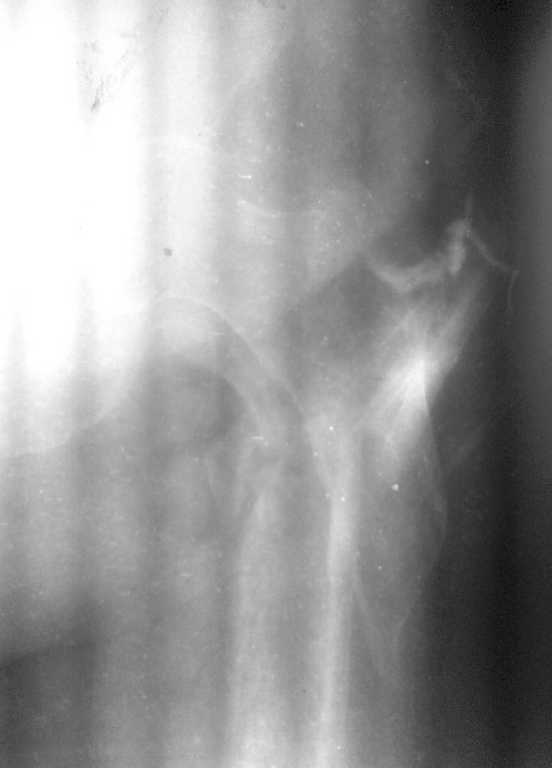

Сразу прошу прощения за качество фистулограммы...лучшего качества не можем добиться.

Фистула функционирует от случая к случаю - последние 2 дня выделений небыло, сделали контрастирование (с трудом вошло 5 мл контраста). Признаков воспаления в зоне поражения нет, лабораторные показатели в пределах нормы. Судя по распростарнению контраста - локальный остеомиелит в месте расположения стержня АВФ

План следующий: 1.контрастирование зелёнкой, ФНСЭ, дренирование+бусы с антибиотиком

2. если нет распространеия контраста в область грушевидной ямки и места перелома - БИОС стержнем с цементным покрытием

3. если распространение в указаные области есть - дренирование, бусы, заживелние раны, дистракция отломков, БИОС